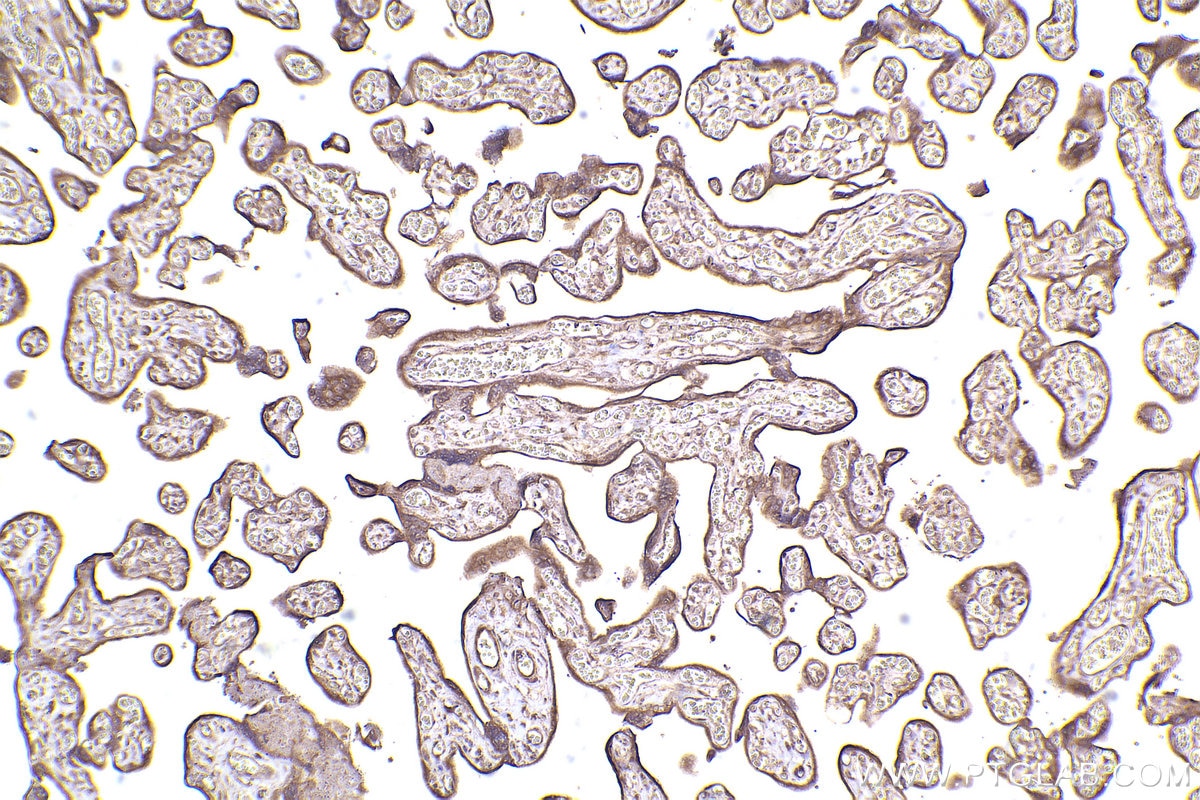

| Positive IHC detected in | human placenta tissue, human lung cancer tissue Note: suggested antigen retrieval with TE buffer pH 9.0; (*) Alternatively, antigen retrieval may be performed with citrate buffer pH 6.0 |

| Immunohistochemistry (IHC) | IHC : 1:500-1:2000 |